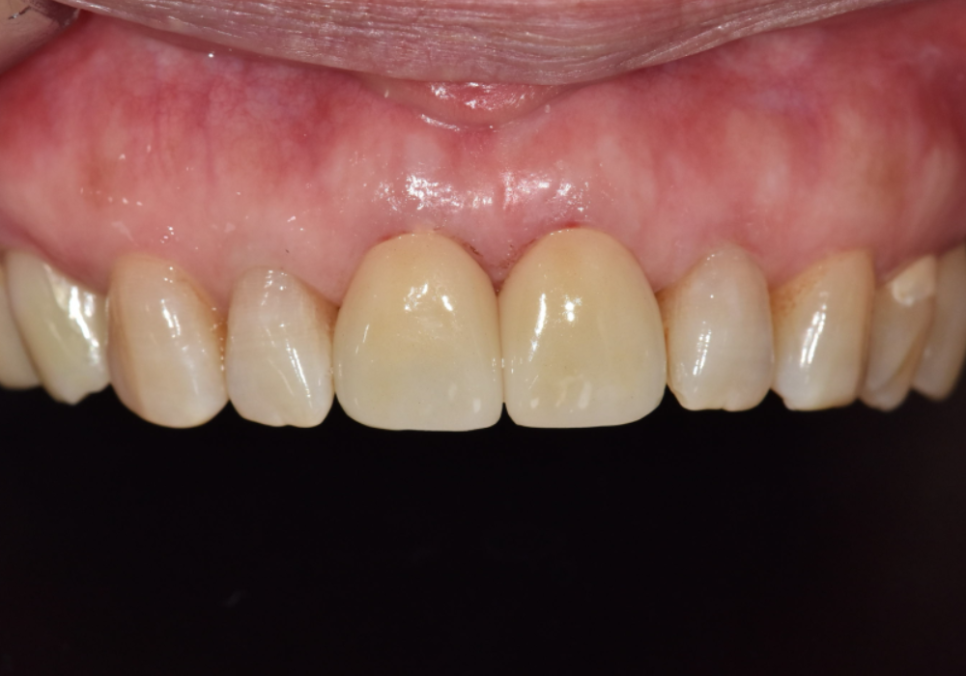

결국 안전하게 치아를 보호해 주는

지르코니아 크라운으로

치료를 도와드렸어요.

260311 / 260325

앞니 사이가 벌어져 고민이셨던 부분까지

세밀하게 반영하여 자연스럽게

마무리해 드렸습니다.^^

260325